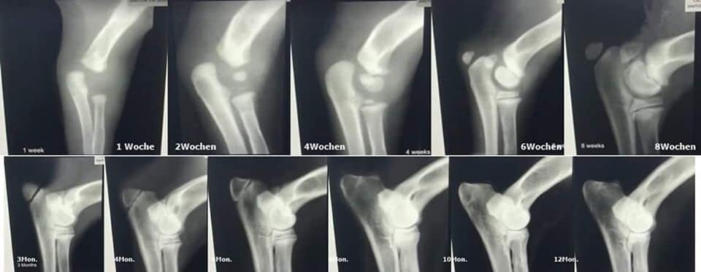

Was prägt Welpen fürs Leben? Was bedeutet Prägung überhaupt? Wenn Sie das Wort „Prägung“ mal im Internet eingeben werden Sie feststellen, dass es verschiedenste Definitionen gibt. Im Zusammenhang mit der Hundehaltung spricht man eher von „prägeähnlichen Lernprozessen“. Dies liegt daran, dass im wissenschaftlichen Sinne Prägung ein unumstößlicher Lernvorgang ist. Hunde jedoch können ihr Verhalten verändern und daher ist einmal Erlerntes keineswegs irreversibel. Um es nicht unnötig kompliziert zu machen, lassen wir die Wissenschaft außen vor und nennen den Begriff nachfolgend dennoch Prägung. Die Neonatale- und Übergangsphase Jeder Züchter und jeder Welpenbesitzer legt größten Wert darauf, seinen Welpen bestens aufs Leben vorzubereiten. Von Geburt an ist es für den Welpen wichtig, dass er durch sein genetisch fixiertes Verhalten positive und negative Erfahrungen macht. Welpen können trotz verschlossener Ohrkanäle Schreckreaktionen auf laute Geräusche zeigen, warm und kalt unterscheiden und auch Schmerzreaktionen zeigen. Milder Stress ist hier das Zauberwort. Dieser fördert das Immunsystem und befähigt den Organismus mit Stress und Belastung umzugehen. Zum Ende der 3. Lebenswoche bekommen Umweltreize eine Bedeutung für den Welpen. Seine Motorik wird kontrollierter und die Schlafperioden werden kürzer. Die Sozialisationsphase beginnt In dieser Phase finden wichtige Wachstums- und Differenzierungsprozesse im Gehirn statt und sorgen so dafür, dass sich die Neuronen im Gehirn untereinander vernetzen und der Welpe somit besser lernen kann. Ganz besonders wichtig ist es in dieser Phase, ihn weder in Watte zu packen noch zu überfordern. Bieten Sie ihm die Möglichkeit Kinder, ältere Menschen und Erwachsene kennen zu lernen oder auch Erfahrungen im Garten zu sammeln. Besonders sollten Sie in dieser Phase darauf achten, dass der Welpe sich selbstständig in verschiedenen Situationen bewegen und darf. Der Welpe soll eigenständig lernen… Demutsgesten zu zeigen, mit Angst fertig zu werden, seine Zähne dosiert einzusetzen, Aggressionen und Frustrationen abzubauen, und nach Lösungen zu suchen. Der Welpe muss lernen, sein Verhalten der Situation anzupassen Nicht alles im Leben läuft so, wie er es wünscht und deswegen geht die Welt nicht unter. Diese Lernvorgänge sind für ihn äußerst wichtig, um im späteren Leben seine Reaktionen dem Kontext anpassen zu können. Der kleine Kampf mit seinen Geschwistern an der Futterschüssel, ist für diesen Lernprozess zum Beispiel sehr zuträglich. Ein ständig reichhaltiges Futterangebot würde den Lernprozess unterbrechen. Züchter und Welpenbesitzer müssen die Prägung fortsetzen Studien belegen, dass Welpen die sowohl beim Züchter als auch beim künftigen Welpenbesitzer betont ruhig aufwachsen, später die gelasseneren Hunde sind. Viele bekommen plötzlich wahnsinnigen Stress Auf einmal denken Sie an die Sozialisationsphase und meinen, sie müssten noch so viel erledigen. Der Welpe soll Busfahren, die Stadt kennenlernen, jegliche Menschen und Tiere in der Nachbarschaft erleben und und und… All dies kann einen Welpen ganz schön überfordern Wir sollten unsere Ansprüche wirklich umsichtig dem einzelnen Welpen und der zukünftigen Lebenssituation anpassen. Wer bekommt den Welpen? Welche Ansprüche haben Sie? Möchten Sie einen ruhigen oder agilen Hund? Dementsprechend sollte auch seine Förderung angepasst sein. Wenn Züchter sich zu starke Mühe geben und dem Welpen alle Umweltsituationen aussetzen wollen, wird ihn später wenig beeindrucken. Der Mittelweg ist auch hier wieder ideal. Nehmen Sie sich Zeit Bei all dem Freizeitstress, dem Welpen häufig ausgesetzt sind, wird eines gerne vergessen: Welpe und Familie müssen sich kennen lernen, um eine Bindung zueinander aufbauen zu können. Dazu sind die alltäglichen Situationen in der Regel für alle Beteiligten schon Herausforderung genug. Welpengruppen, Café und was es sonst noch so gibt, sollte da zunächst nebensächlich sein. Nur Sie und Ihr Welpe zählen und seien Sie gewiss: Ihr Welpe wird auch später noch lernen können Bus zu fahren. Sorgen Sie zunächst für eine gute Mensch-Hund –Beziehung. Wenn das stimmt, dann kann die Erziehung anfangen. Das A und O der Bindung Hundehalter verstehen unter Bindung Unterschiedliches. Während die Einen Bindung mit Erziehung verwechseln, verstehen die Anderen darunter, dass der Hund die Nähe seines Menschen sucht. Doch Bindung ist viel mehr als das. Bindung ist ein unsichtbares Band Egal ob in der Tierwelt oder bei uns Menschen: Schon die Kleinsten lernen, sich zu binden, wobei man Bindung keinesfalls mit Abhängigkeit verwechseln darf. Die kindliche Abhängigkeit nimmt im Laufe des Lebens ab, wobei die Bindung ein Leben lang bestehen kann. Warum binden sich Lebewesen? In der Tierwelt dient Bindung schlichtweg dem Überleben. Gemeinsam ist man stark und daher kommen als Bindungspartner ausschließlich Jene in Frage, die man gut kennt und auf die man sich verlassen kann. Genau wie wir Menschen, suchen auch Hunde nach Sicherheit und Geborgenheit. Wissenschaftler haben heraus gefunden, dass diese ähnlichen Bedürfnisse, die vertrauensvolle und tiefe Bindung zwischen Mensch und Hund erklären. Hat Bindung etwas mit Nahrung zu tun? Absolut nicht. Zwar schätzen unsere geliebten Vierbeiner Hundekekse sehr, jedoch sind sie nicht verantwortlich für eine tiefe Bindung. Vielmehr ist die Sicherheit, Geborgenheit und Akzeptanz wichtig für eine gute Bindung. Das erklärt auch, warum sowohl Hund als auch Kind in einer Gefahrensituation sofort zur Mutter oder zum Hundebesitzer laufen. Wie erreichen Sie eine gute Bindung zu Ihrem Hund? Fühlt ihr Hund sich unsicher oder hat er sogar Angst, wird er versuchen durch fiepen, bellen, heulen, lecken, anstubsen, Körper- oder Blickkontakt Nähe zu Ihnen herzustellen. Reagieren Sie auf diese Zeichen angemessen und selbstsicher. Sofort wird ihr Hund sich sehr viel besser fühlen. Verletzt sich Ihr Tier, reagieren Sie sofort, um ihm zu helfen. Beantworten Sie seine Zeichen, wie zum Beispiel Blickkontakt, stets mit einem freundlichen Wort. Zeigen Sie Ihrem Hund, dass Sie ihn wahrnehmen und schätzen. Seien Sie feinfühlig und dies immer, dann können Sie ein unsichtbares Band aufbauen, welches ein Leben lang erhalten bleibt. Welche Fehler kann man machen? Verwechseln Sie Bindung nicht mit Erziehung! In der Erziehung ist es die wohlgemeinte Konsequenz, die ans Ziel führt. Bei der Bindung ist es das Gefühl und Ihre Feinfühligkeit, was Sie verbindet. Reagieren Sie stets angemessen auf das Verhalten Ihres Hundes. Droht Gefahr schreiten Sie ein, aber lassen Sie sich zum Beispiel im Restaurant nicht von bettelnden Gesten beeindrucken. Dies betrifft nicht die Bindung, sondern ganz klar die Erziehung. Würden Sie in der Situation auf Ihren Hund eingehen oder gar ihm nachgeben, dann hat er sicherlich eines gelernt: Dass sein Verhalten erfolgreich war. Aber die Bindung bleibt davon unberührt. Fazit: Jeder schätze sich glücklich, den eine tiefe Bindung zu seinem Hund verbindet. Arbeiten Sie ein Leben lang daran. Dies lohnt sich, denn Sie werden reichlich dafür beschenkt. Wieviel Bewegung braucht ein Welpe ?? Golden Retriever Welpen befinden sich in den ersten 18. Monaten in einem Stadium der Knochenentwicklung. In dieser Zeit sind die Knochen sehr empfindlich, da sie noch weich sind dadurch nur wenig belastet werden sollten. Es gibt einige Punkte, die man unbedingt einhalten sollte: Absolutes Treppen-Verbot, tragen sie ihren Welpen also so lange es geht die Treppen auf und ab. Der Welpe muß unbedingt Ruhepausen mache, fordern sie ihn niemals zum Spielen auf, wenn er gerade schläft Vermeiden sie extreme Bewegungen, dazu gehören Spurts mit schnellen Stop Niemals an den Beinen oder der Rute ziehen Lassen sie den Welpen über keine Hindernisse springen - kein Agility bevor er 18. Monate alt ist. Beiss-Reiss Spiele vermeiden, sie können zur Gebißverformung führen Keine Fahrradtouren bevor der Hund ausgewachsen ist. Lassen sie ihn lieber auf einem Feld oder Wiese toben, der weiche Boden tut den Gelenken gut, auch Traben ist besser als Galoppsprünge. 5-Minuten Regel ein Welpe soll täglich nur 5 Minuten je Lebensmonat Bewegung haben. Körperliche Überanstrengung in Kombination mit hochkalorienhaltiger Fütterung führt neben dem genetischem Aspekt oft zu Gelenkerkrankungen wie HD/ED. Bewegen Sie im ersten Lebensjahr ihren Welpen lieber zu wenig als zu viel. Passen Sie das Tempo der Gassirunde an - ein strammer 20-minütiger Weg kann schon zu viel sein !